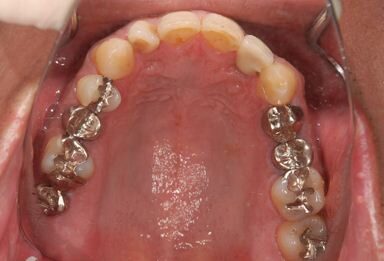

抜歯即日スピードインプラント治療

| 性別/年齢 | 男性 / 36歳 | ||||||||||||||||||||||||||||||||

| 主訴 | 前歯が折れていてないので、インプラント治療を希望。 | ||||||||||||||||||||||||||||||||

| 治療内容 | インプラント1本(抜歯即日スピードインプラント)、ハイブリッドセラミッククラウン1本 | ||||||||||||||||||||||||||||||||

| 総治療費 | 257,250円 | ||||||||||||||||||||||||||||||||

| 治療期間 | 7ヶ月 |